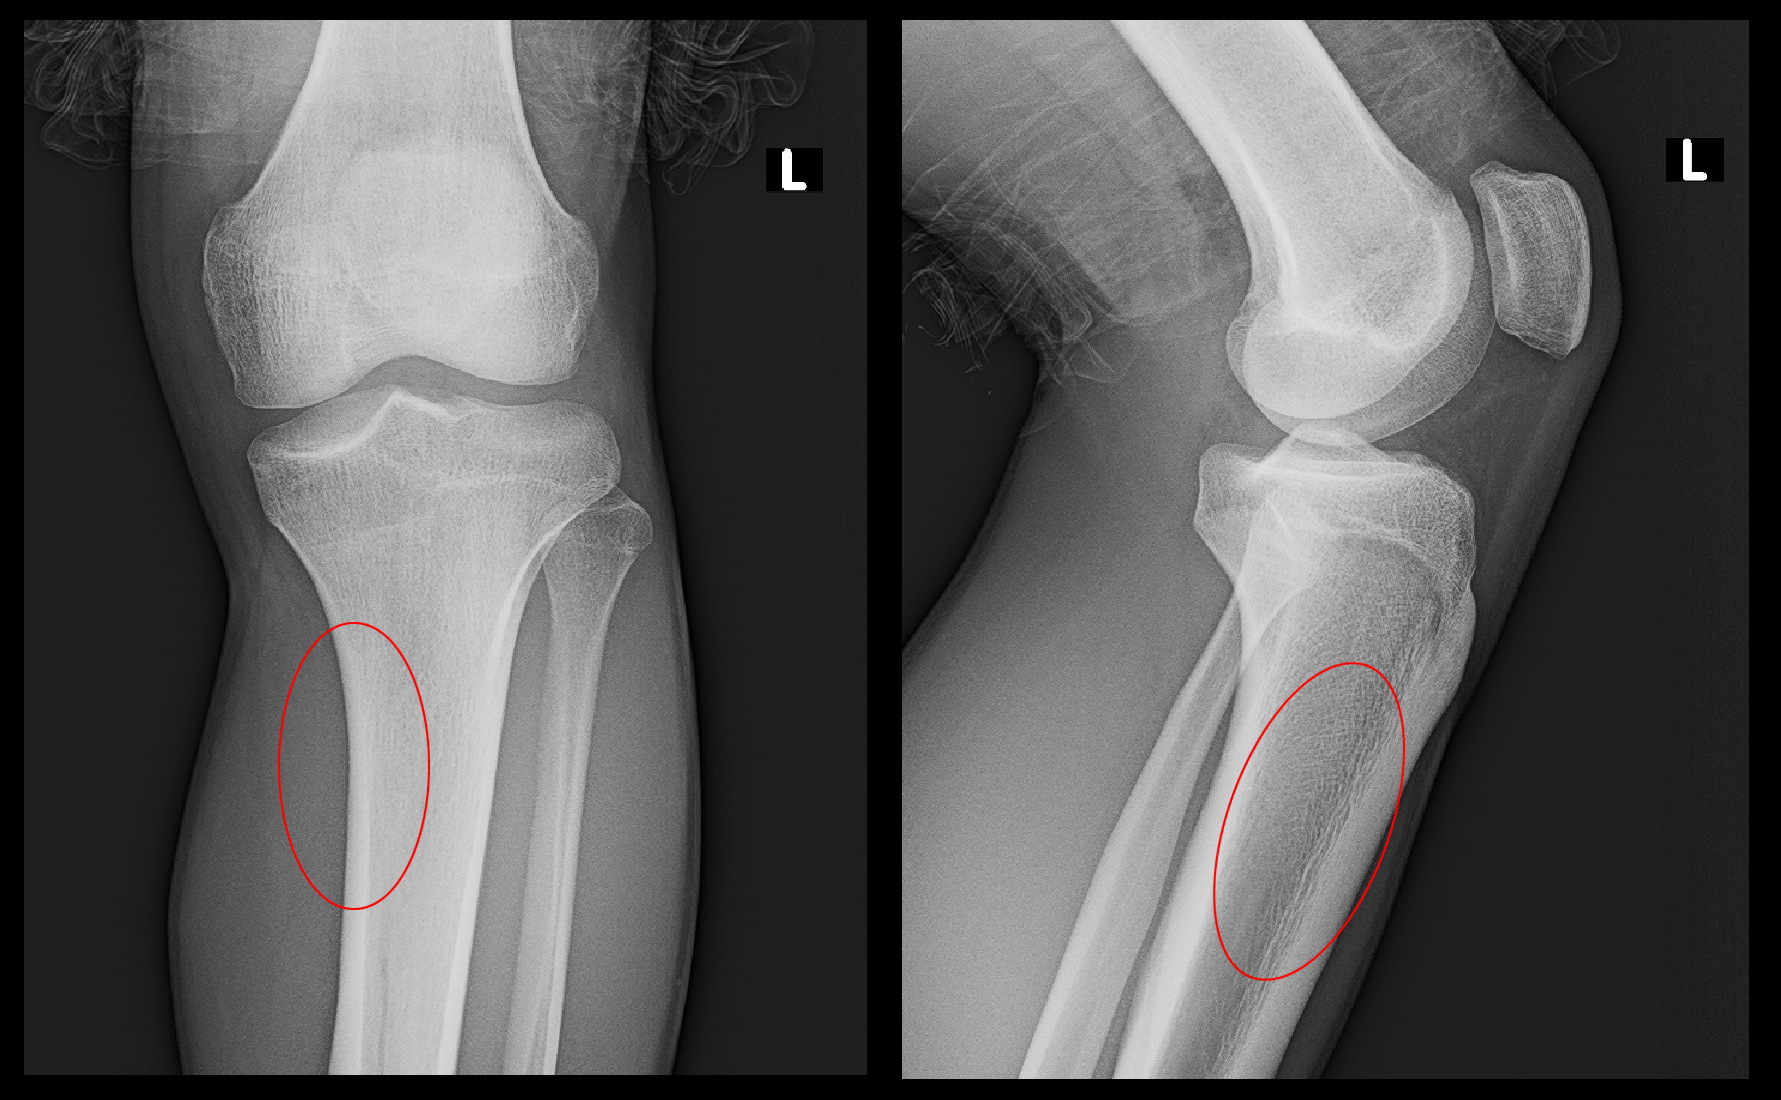

3.5か月後のXp.jpg

2か月後からウォーキングを開始し、X+1年2月29日時点で運動を行っても痛みはなくなったと述べていました。